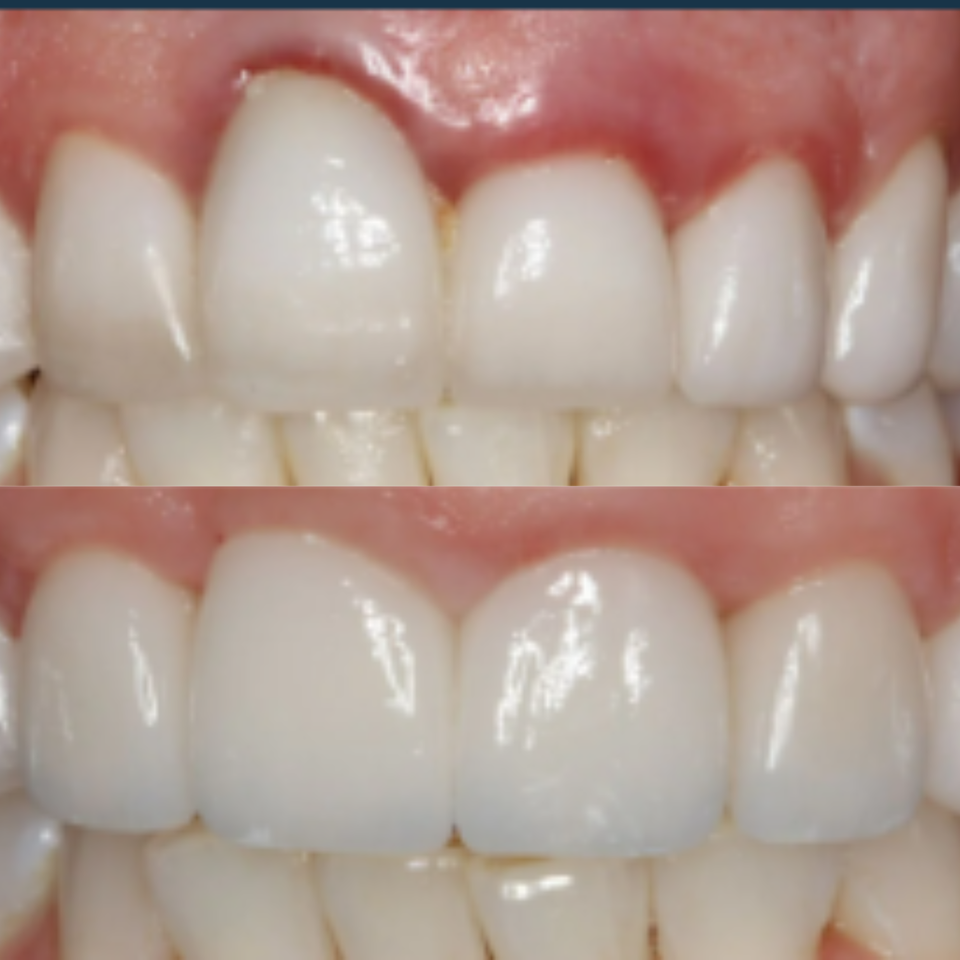

This patient presented with significant gum recession affecting the right central tooth, which ultimately required extraction.

Our team carefully planned and executed the placement of an implant supported crown to achieve a natural looking, fully functional esthetic result. The final outcome not only restored the patient’s smile, but also renewed their confidence.